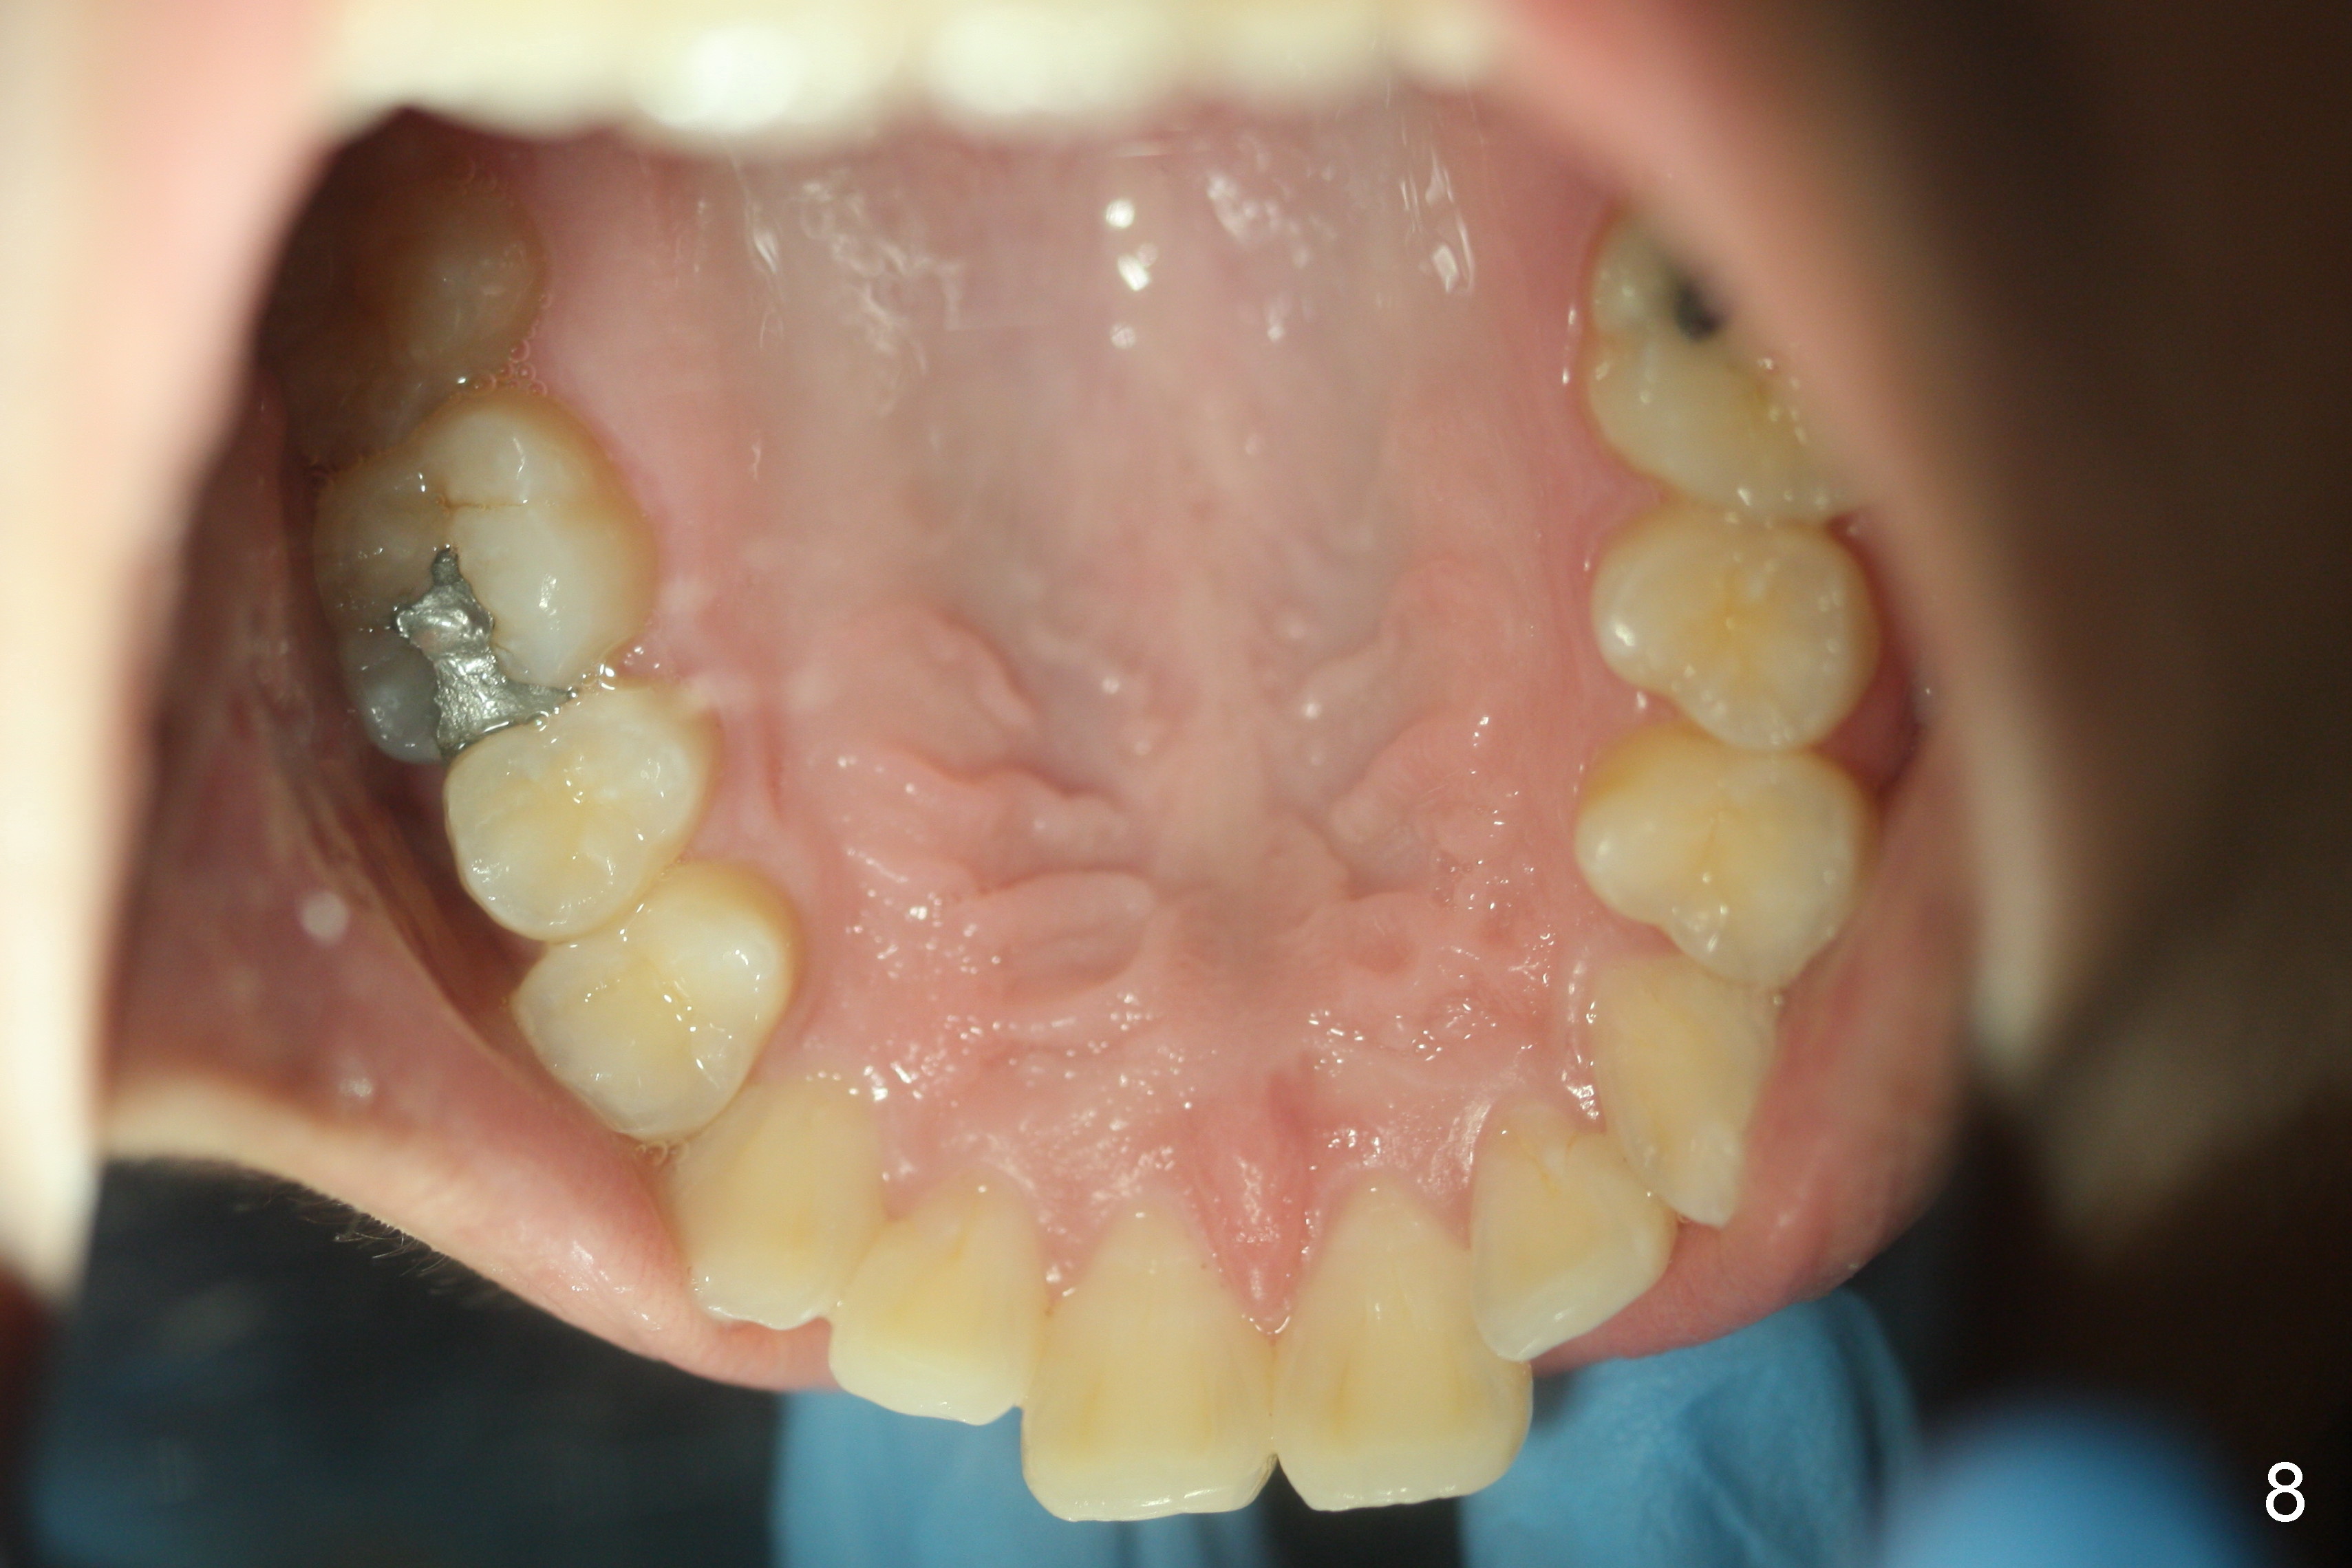

A 15-year-old man wants to improve the facial appearance.

Xin Wei, DDS, PhD, MS 1st edition 02/27/2017, last revision 09/09/2018